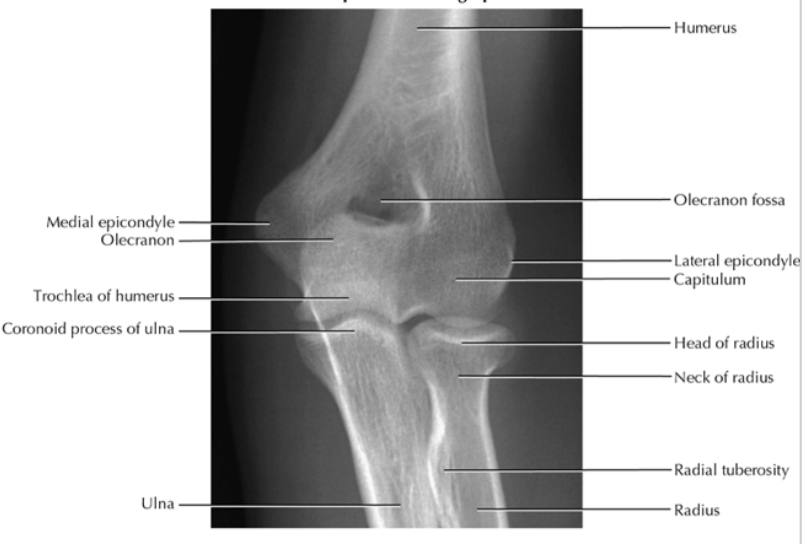

what do you see?